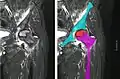

التصوير الومضاني للعظام والرنين الغناطيسي هما الوسيلتان الأفضل لتشخيص المرض في مراحله المبكرة.

صور الأشعة السينية عادة ما تبدو طبيعية في تلك المراحل المبكرة. بينما تبدو المناطق المصابة معتمة نسبيا في المراحل اللاحقة نتيجة لارتشاف الأنسجة العظمية الحية المجاورة بسبب رد الفعل الاحتقاني. العظام النخرية نفسها لا تزيد عتامتها الإشعاعية، لأن العظم الميت لا يمكن أن يخضع لارتشاف العظم الذي تقوم به خلايا الأستيوكلاست الحية.[2] من العلامات التي تظهر في الآشعة في وقت متأخر أيضا منطقة منفذة للآشعة بعد انهيار المنطقة التحت غضروفية للعظم (علامة الهلال) ومناطق حلقية معتمة ناتجة عن تصبن وتكلس دهون نخاع العظام بسبب الاحتشاء النخاعي.